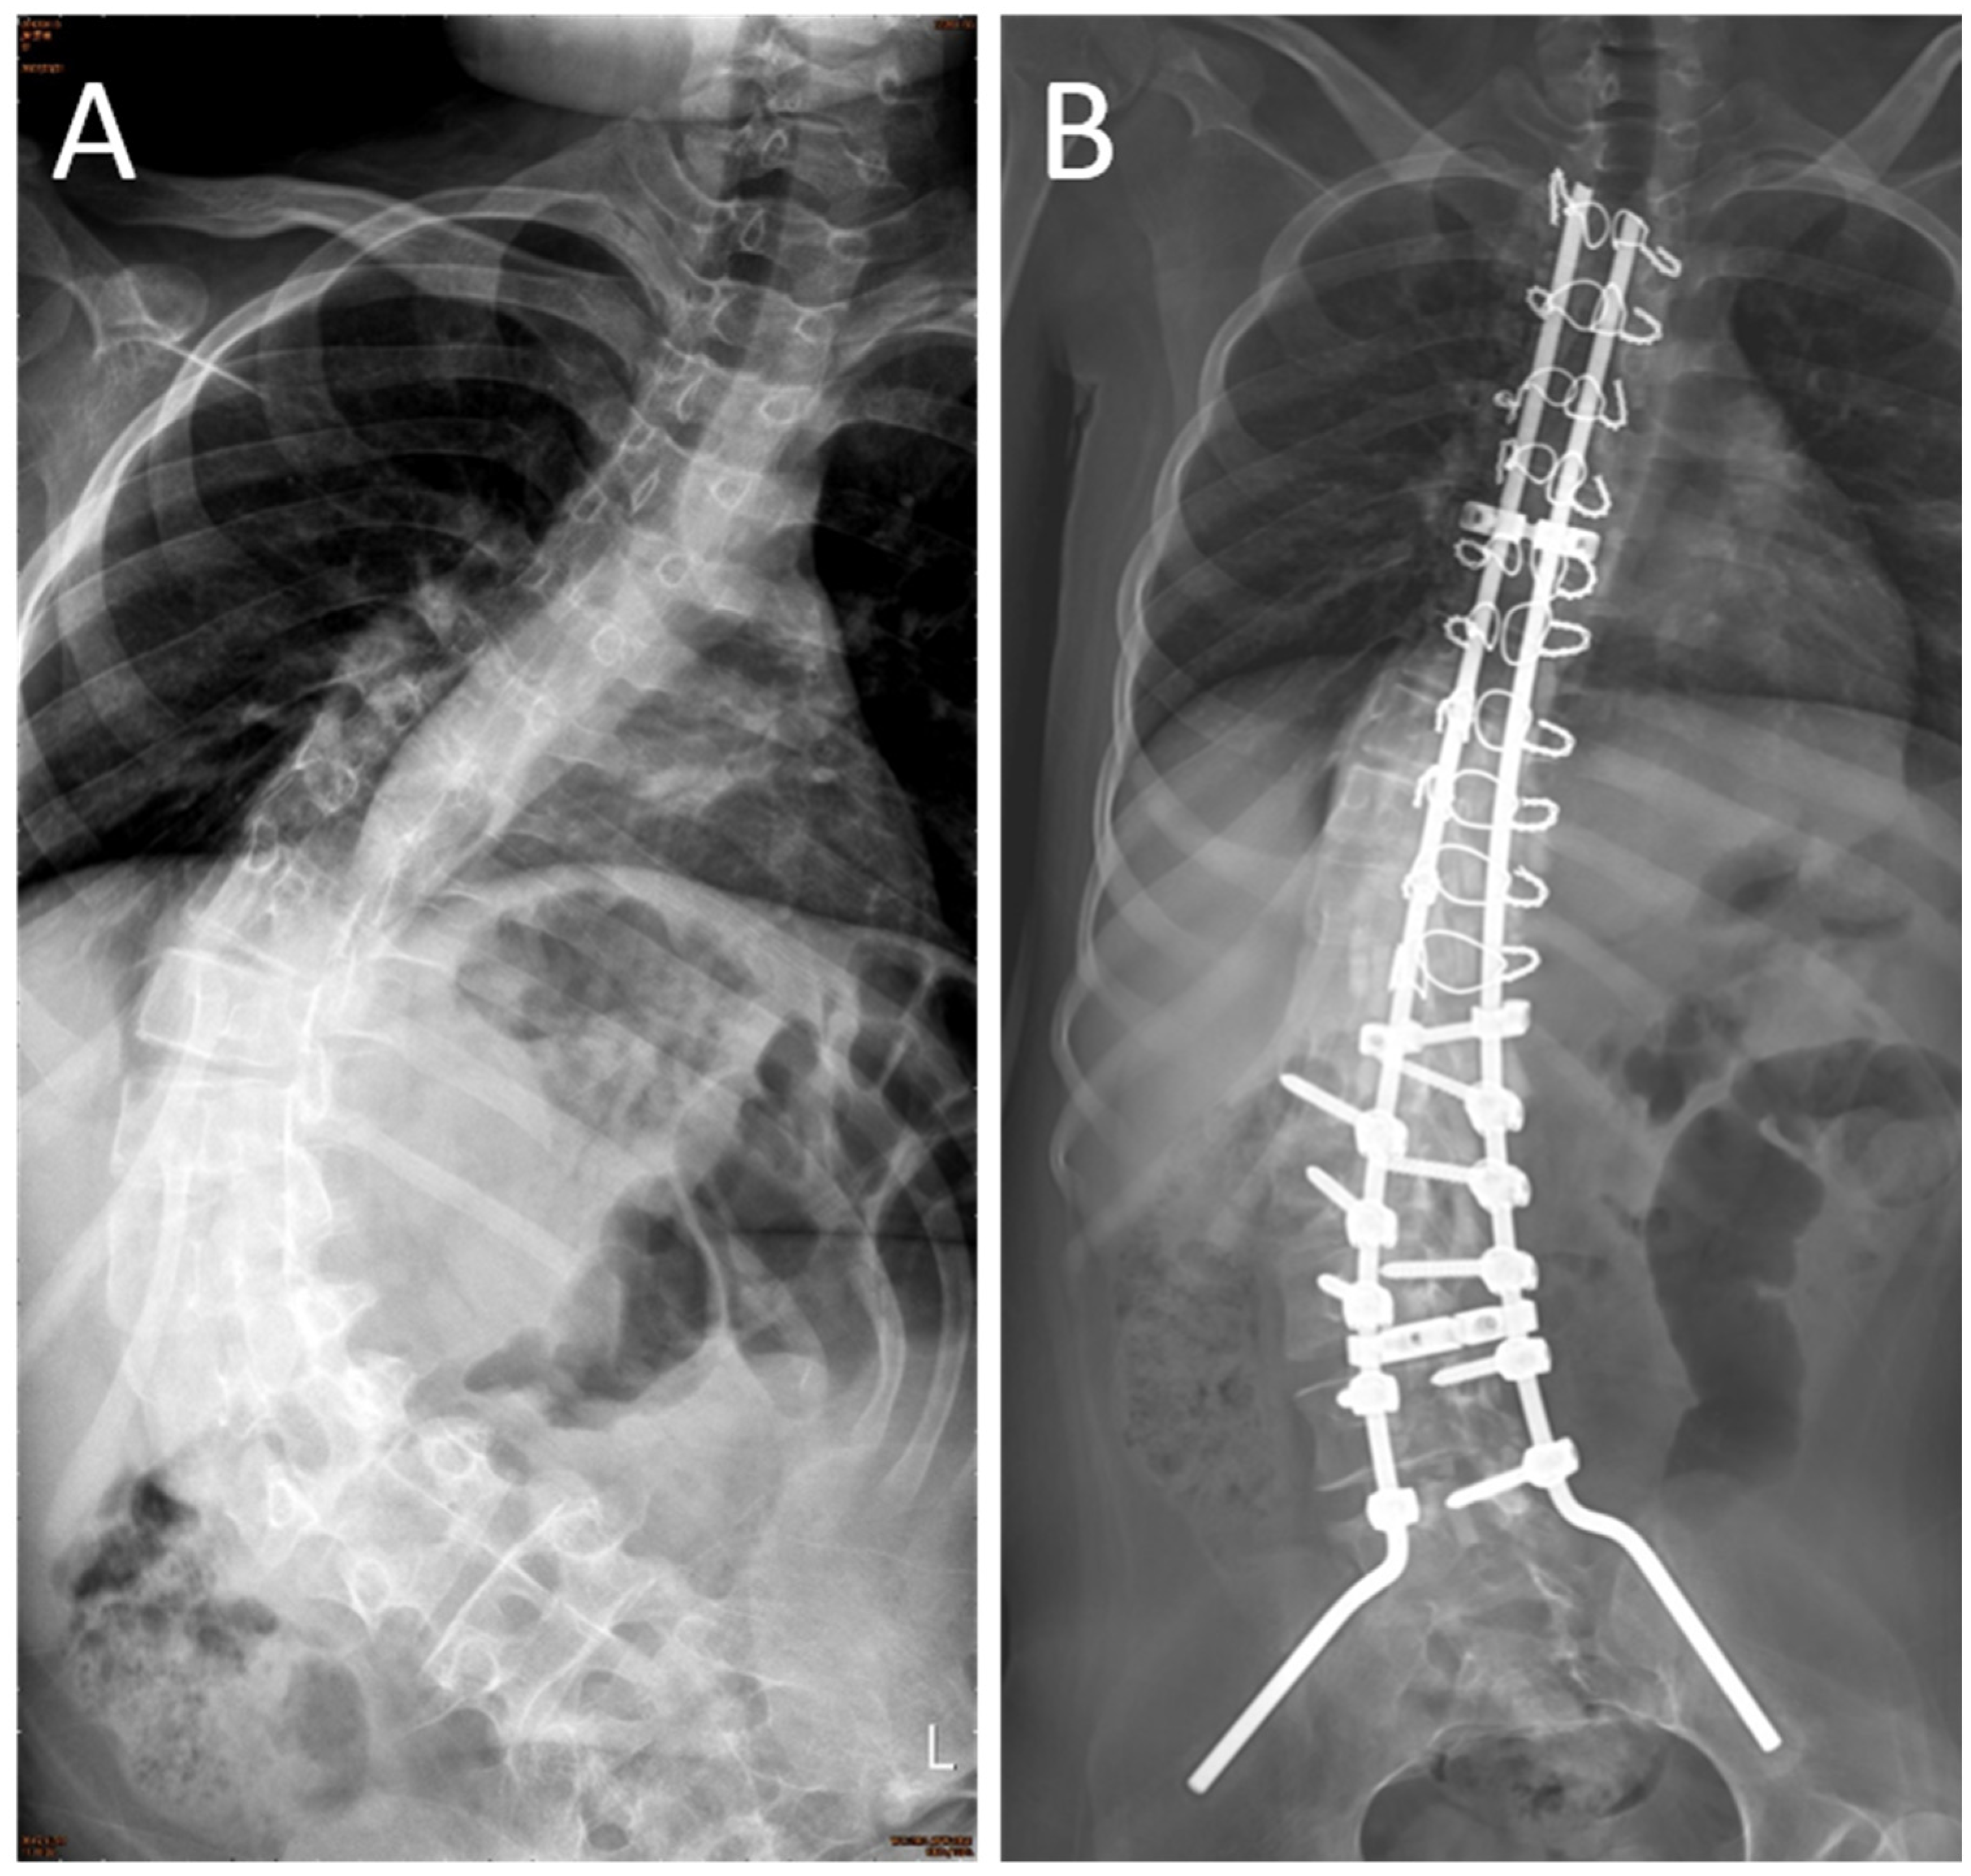

:1. Introduction

2.3. Surgical Procedure